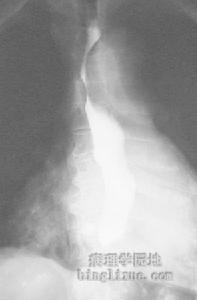

2.腹部X线平片常有肠黏膜增厚、小肠胀气,部分肠麻痹病人表现为肠梗阻。钡灌肠可能发现肠管边呈毛刷状、指压迹症和散在的圆形、不规则形充盈缺损。气钡双重造影可提供更多的诊断指标,但必须小心操作防止肠穿孔的发生。